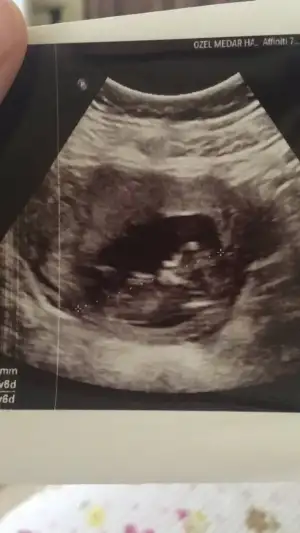

İlk iki foto alttan bakılandan son foto normal daha öncede atmıstım ama cok belli değil demiştiniz bu şekilde bi tahmin olabilirmi Ikra meyra Ikra meyra ☺️

Bir de bunu verdi doktor. Sanırım bacak arası ve kenardakiler de bacakları burada. 11+6 idim.